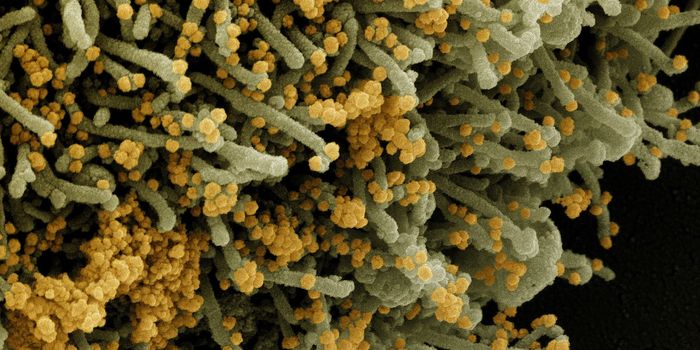

MAY 10, 2021MicrobiologyThe pandemic virus SARS-CoV-2 has changed the world in devastating ways, taking hundreds of thousands of lives & new var ...